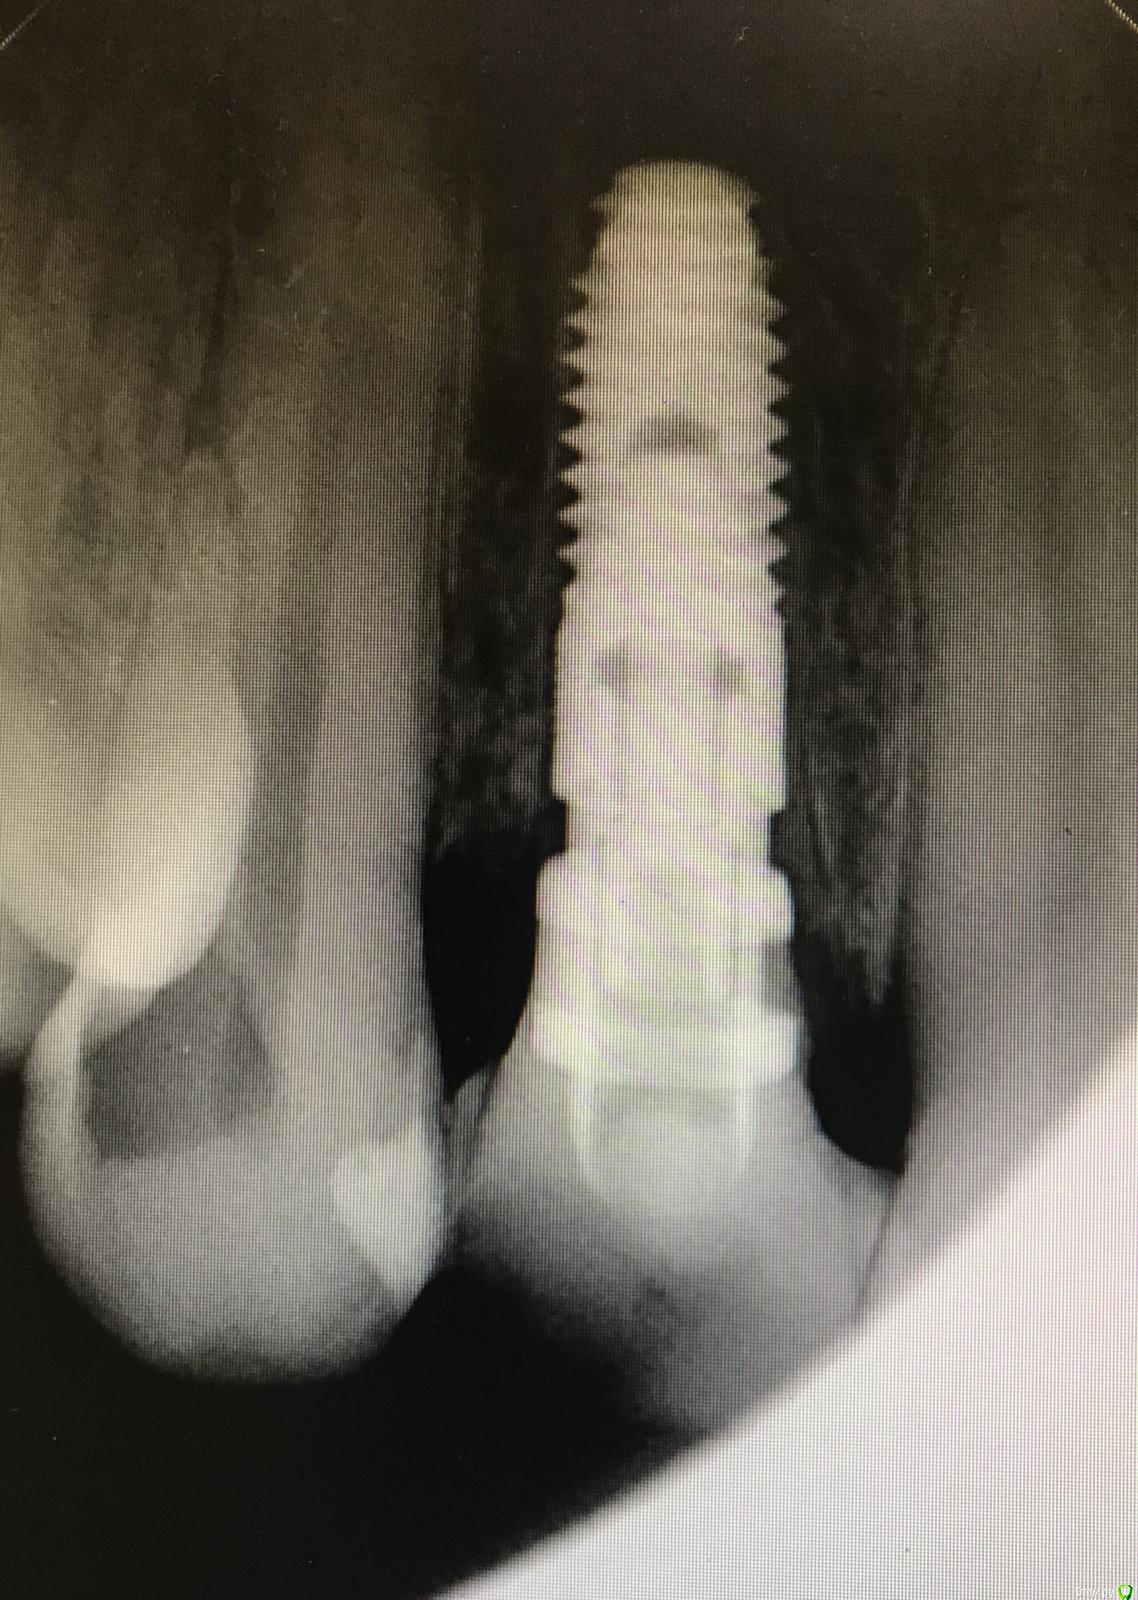

колесников Опубликовано 25 октября, 2017 Поделиться Опубликовано 25 октября, 2017 Лучше с нагрузкой. Сразу понятна будет позиция импланта относительно окончательной реставрации,если что -то не понравится можно пересверлиться, одновременно формируется профиль десны. Консоль с овоидом,работа получится супер. Незабудьте зашинировать к соседним зубам ,лучше армировать. Если пациент отнекивается ,не хочет тратиться на временную конструкцию,используйте имплантовод анкилос как временный абатмент. Вот как пример реставрация на имплантоводе семадос и армированный имплант с консолью. 1 Ссылка на комментарий